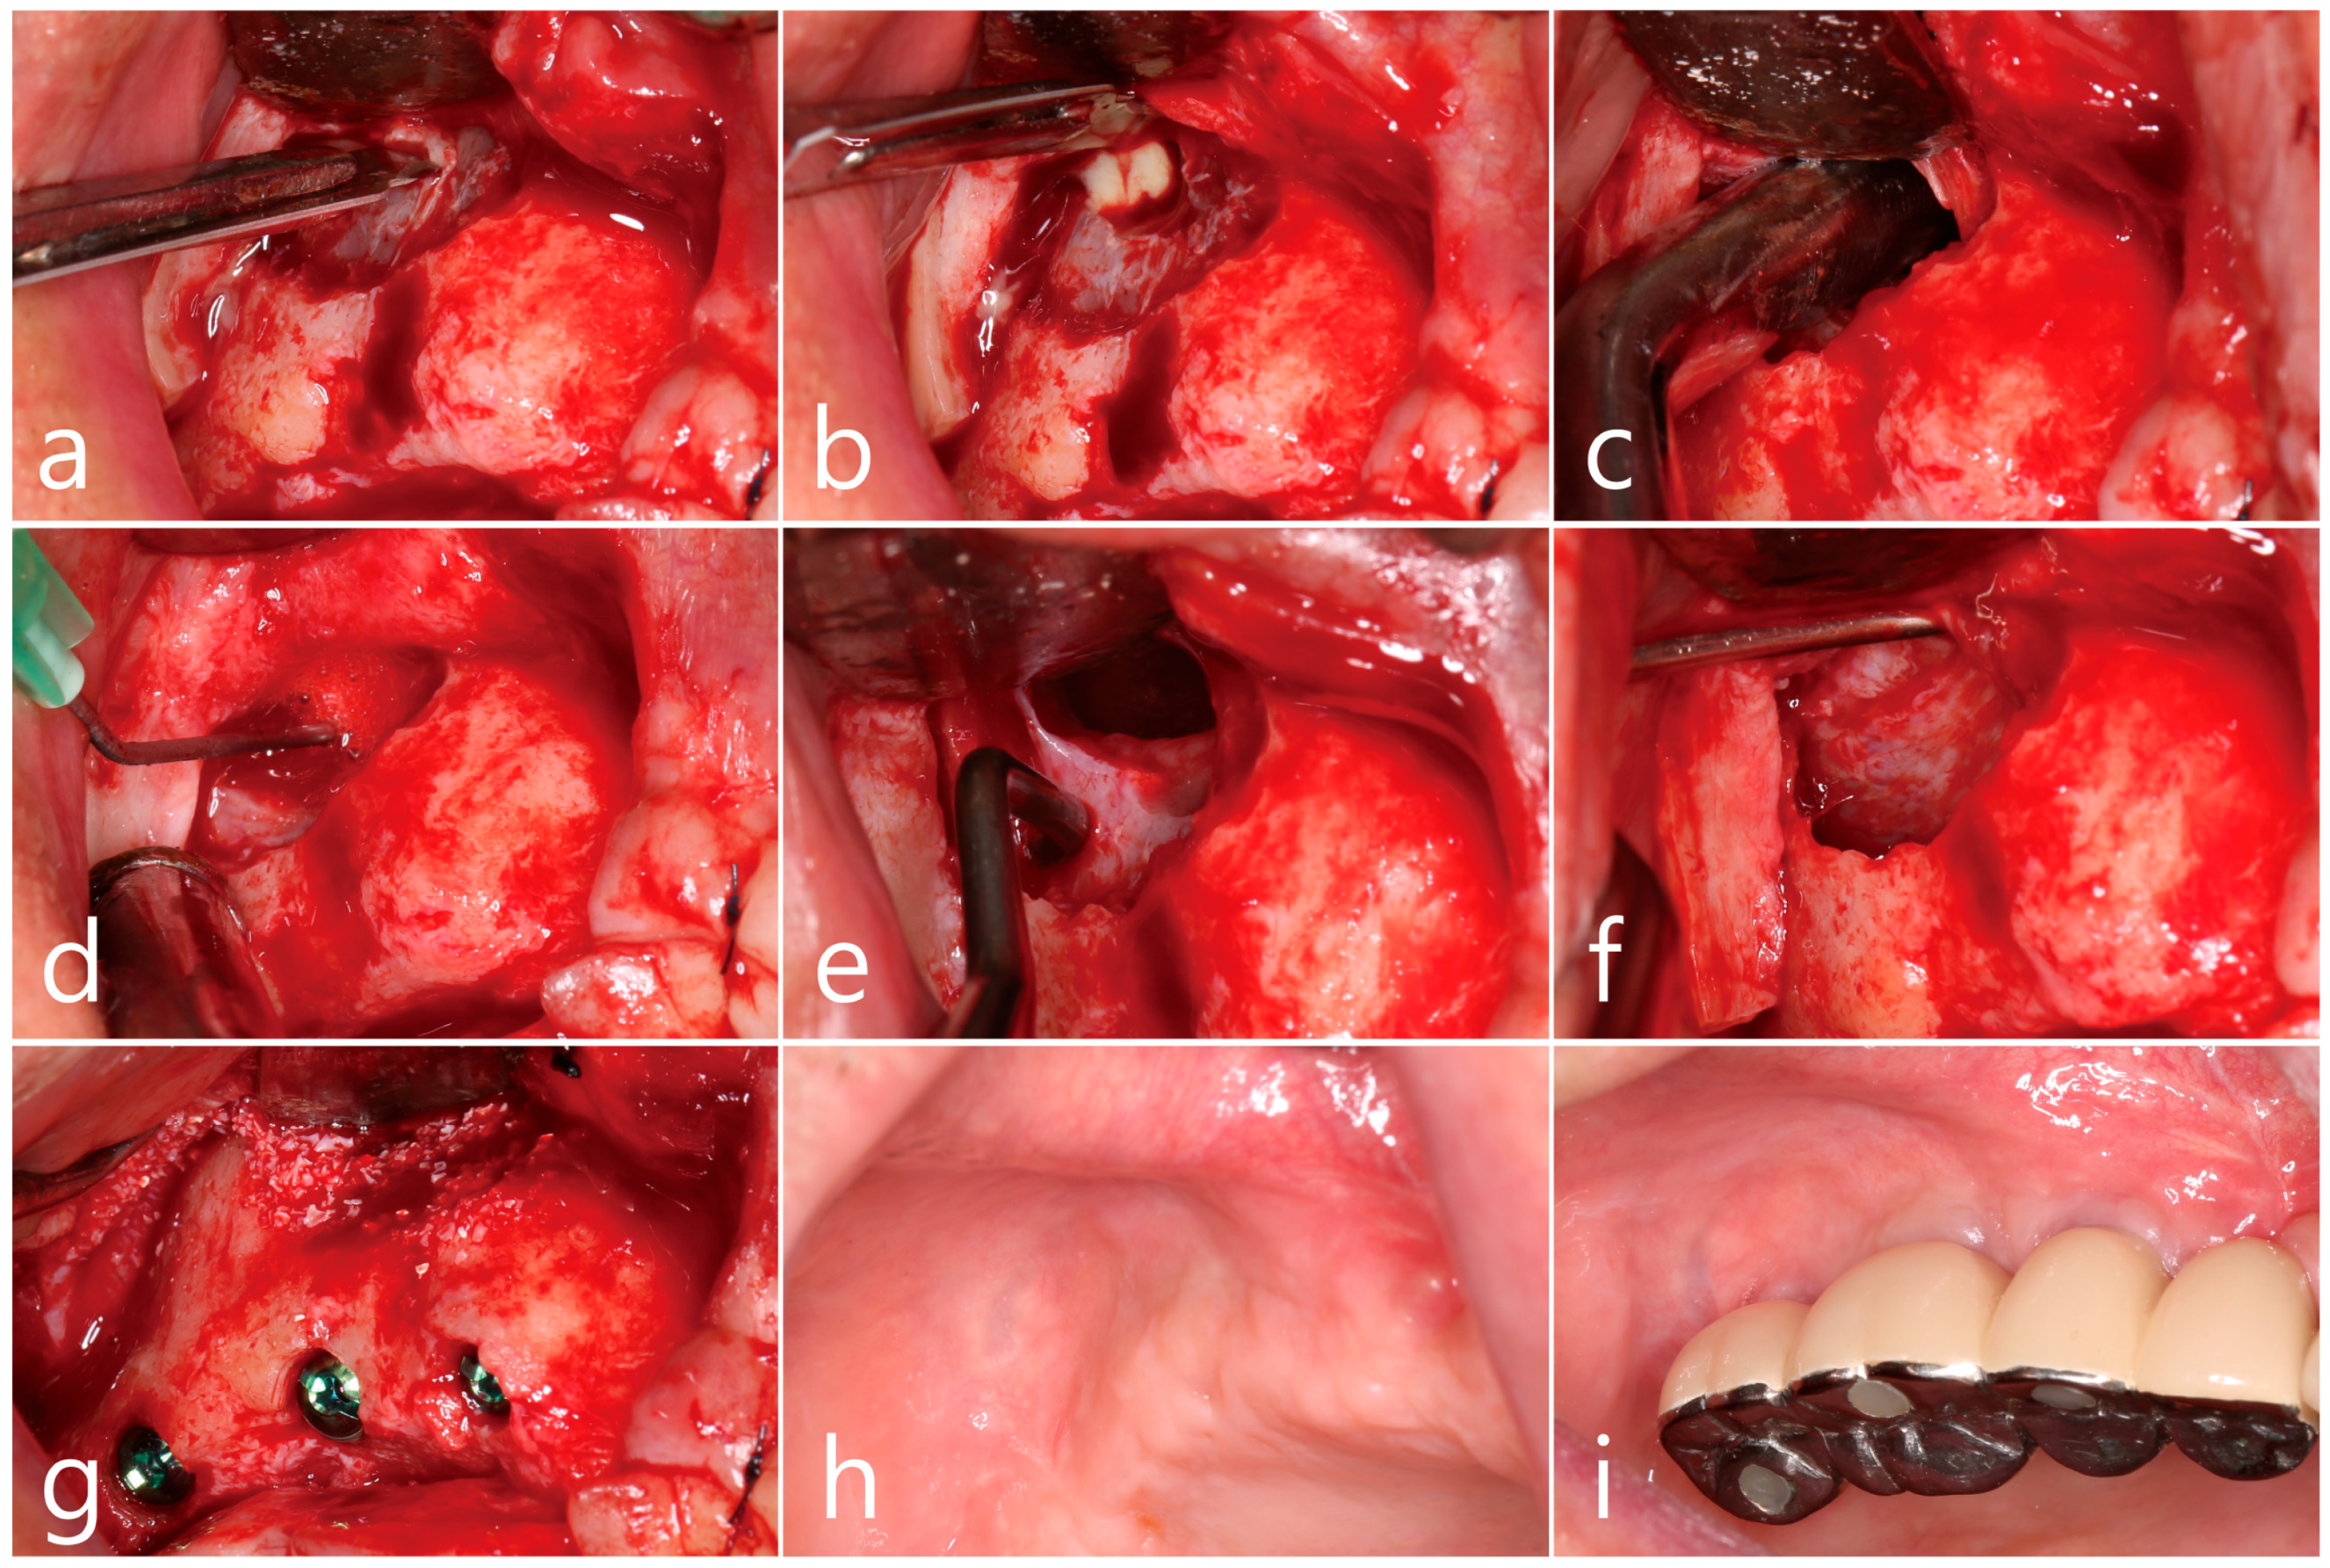

2.1. Case 1